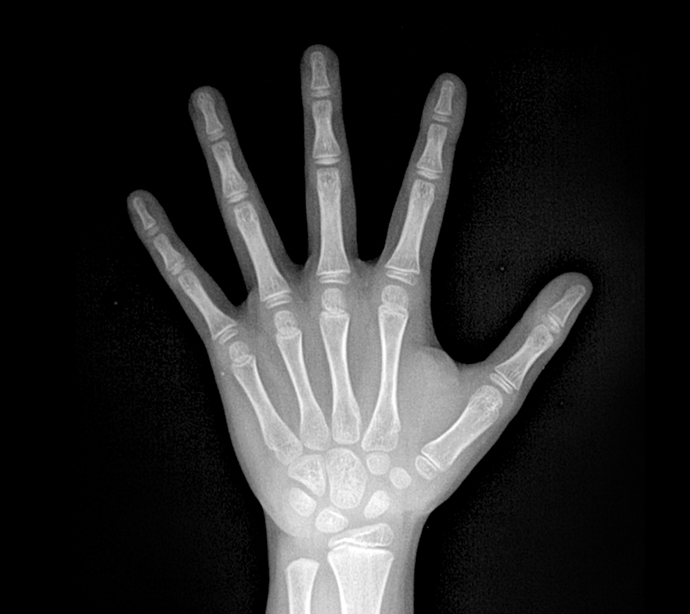

손과 손목 X-ray를 찍습니다. 서대문정형외과에서는 골연령 평가 방식의 대표적인 Tanner-Whitehouse 3(TW3)와 Greulich-pyle(GP)의 장점을 통합한 방식의 인공지능 기법을 사용하여 분석합니다.

손, 손목 X-ray로 골연령을 분석한 후 실제나이(역연령)에 비해 뼈나이(골연령)의 진행이 어떠한지 알아보고 아이가 향후 어느정도 클 수 있을지 예측해 보게 됩니다. 전세계적으로 가장 많이 사용되는 AHP와 BP 두가지 방식으로 성인 예측키를 분석합니다.